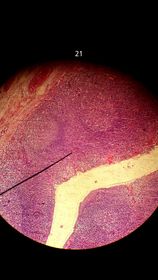

Médula Ósea